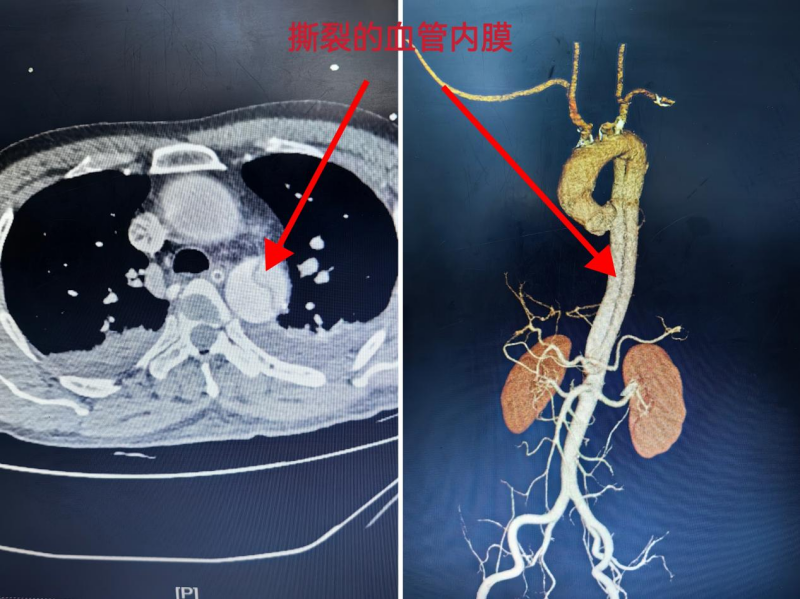

患者卓某,因上3米高树摘八角不慎坠落至全身多处伤。伤后至蒙山县中医院就诊,经检查后,发现卓某肝破裂、横结肠系膜破裂伤及右侧肋骨骨折伴血气胸,在该院予抗感染、抗休克、胸腔闭式引流、急诊手术行肝脏、结肠系膜止血等处理,结合腹部CT等结果,还发现卓某有主动脉血管壁内膜的撕裂,血液涌入形成了主动脉夹层。这是一种极其凶险的血管疾病,随时可能因夹层破裂导致大出血,危及生命。蒙山县中医院立即联系自治区南溪山医院血管外科团队,请求协助救治。

接到求助后,自治区南溪山医院迅速启动跨院急救绿色通道。血管外科、综合重症医学科、麻醉科等多学科专家组成的应急团队第一时间就位,在转运途中,两院专家通过远程医疗系统实时沟通患者病情。患者送达南溪山医院后,早已待命的医疗团队迅速完成准备工作,待患者入住重症监护室病情平稳后转入血管外科,由科室主任白韬医师团队为患者实施手术,白主任团队凭借精湛的医术和丰富的经验,精准操作,成功植入支架,并进行弓上分支重建,封闭了主动脉夹层破口,恢复了血管的正常血流。 在医护人员的精心护理下,患者术后状况逐渐稳定,并已顺利出院。患者及其家属对两院合作提供的紧急救治服务表示高度赞扬。